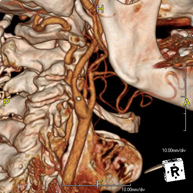

Prueba diagnóstica no invasiva que consiste en el estudio de la arteria aorta abdominal obteniendo imágenes de alta definición anatómica mediante el empleo de un equipo de TC (Tomografía Computarizada) y de contraste yodado. La calidad de las imágenes permite realizar reconstrucciones en 2D y 3D gracias a estaciones de trabajo especializadas en el estudio arterial. Está indicado en aquellos pacientes con enfermedad vascular (aterosclerosis), en aneurismas de aorta, en pacientes con dolor abdominal de posible origen vascular, en estudios pre-quirúrgicos de lesiones adyacentes a la aorta abdominal como "mapa" vascular, etc. La información obtenida de forma no invasiva es indispensable para los pacientes que requieren tratamiento percutáneo o quirúrgico. En aquellos pacientes que solo requieren un seguimiento de las lesiones vasculares, esta técnica es la técnica no invasiva de elección junto con la angio-RM. - Angio-TC arterias renales

Prueba diagnóstica no invasiva que consiste en el estudio de las arterias renales obteniendo imágenes de alta definición anatómica mediante el empleo de un equipo de TC (Tomografía Computarizada) y de contraste yodado. La calidad de las imágenes permite realizar reconstrucciones en 2D y 3D gracias a estaciones de trabajo especializadas en el estudio arterial. Esta prueba está indicada, por ejemplo, en aquellos pacientes que sufren de HTA refractaria al tratamiento, en pacientes con lesiones renales para tener un mapa "vascular" pre-quirúrgico, etc. - Angio-TC aorto-ilíaco

Prueba diagnóstica no invasiva que consiste en el estudio de las arterias ilíacas y la aorta abdominal obteniendo imágenes de alta definición anatómica mediante el empleo de un equipo de TC (Tomografía Computarizada) y de contraste yodado. La calidad de las imágenes permite realizar reconstrucciones en 2D y 3D gracias a estaciones de trabajo especializadas en el estudio arterial. Esta prueba está especialmente indicada como estudio pre-quirúrgico (mapa vascular) antes de intervenciones percutáneas o quirúrgicas de aorta abdominal, como el estudio complementario en pacientes con isquemia de miembros inferiores, etc. - Colonoscopia virtual

Prova diagnòstica no invasiva que consisteix en l'estudi de l'artèria aorta abdominal amb l'obtenció d'imatges d'alta definició anatòmica mitjançant l'ús d'un equip de TC (Tomografia Computaritzada) i contrast iodat. La qualitat de les imatges permet realitzar reconstruccions en 2D i 3D gràcies a estacions de treball especialitzades en l'estudi arterial. Està indicat en aquells pacients que pateixen malaltia vascular (arteriosclerosi), aneurismes d'aorta, en pacient amb dolor abdominal d'un possible origen vascular, en estudis prequirúrgics de lesions adjacents a l'aorta abdominal com el "mapa" vascular, etc. La informació obtinguda de forma no invasiva és indispensable per als pacients que requereixen tractament percutani o quirúrgic. En aquells pacients que només requereixen un seguiment de les lesions vasculars, aquesta tècnica és la tècnica no invasiva d'elecció juntament amb l'angio RM. - Angio TC d'artèries renals

Prova diagnòstica no invasiva que consisteix en l'estudi de les artèries renals amb l'obtenció d'imatges d'alta definició anatòmica mitjançant l'ús d'un equip de TC (Tomografia Computaritzada) i contrast iodat. La qualitat de les imatges permet realitzar reconstruccions en 2D i 3D gràcies a estacions de treball especialitzades en l'estudi arterial. Aquesta prova està indicat en aquells pacients que pateixen HTA refractària al tractament, en pacients amb lesions renals que tenen un mapa vascular prequirúrgic, etc. - Angio TC d'aorta-ilíaca

Prova diagnòstica no invasiva que consisteix en l'estudi de les artèries ilíaques i l'aorta abdominal amb l'obtenció d'imatges d'alta definició anatòmica mitjançant l'ús d'un equip de TC (Tomografia Computaritzada) i contrast iodat. La qualitat de les imatges permet realitzar reconstruccions en 2D i 3D gràcies a estacions de treball especialitzades en l'estudi arterial. Aquesta prova està especialment indicada com a estudi prequirúrgic (mapa vascular) abans d'intervencions percutànies o quirúrgiques d'aorta abdominal, estudi complementari en pacients amb isquèmia de membres inferiors, etc. - Angio TC arterial d'extremitats inferiors